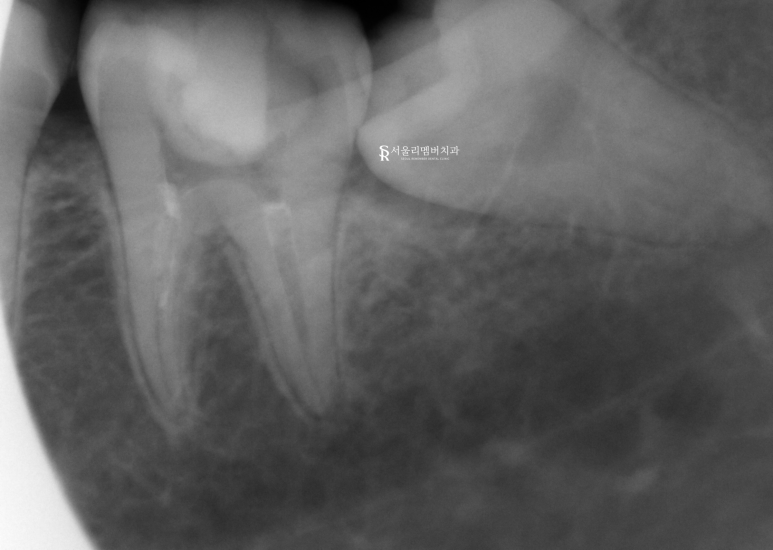

근관치료를 진행했습니다.

어금니는 앞니에 비해 뿌리의 개수가 많고

복잡한 형태를 갖고 있기 때문에

더 주의 깊고 꼼꼼한 시술을 필요로 합니다.

치수에 도달하는 통로를 확보하기 위해

상아질과 법랑질에 퍼져있는 충치를 제거했습니다.

내부에 있는 치수, 근관에 쉽게 접근할 수 있도록

원형의 통로를 뚫어드렸죠.

이후 감염된 곳을 제거한 뒤에

소독제가 곳곳에 퍼질 수 있도록 근관을 확장시킵니다.

염증이 심했기에 좀 더 오래 걸렸네요.

남아있는 병소는 없는지,

감염된 곳은 깨끗하게 제거되었는지

확인 과정을 거친 뒤에

충전재를 사용하여 밀폐를 해주었습니다.